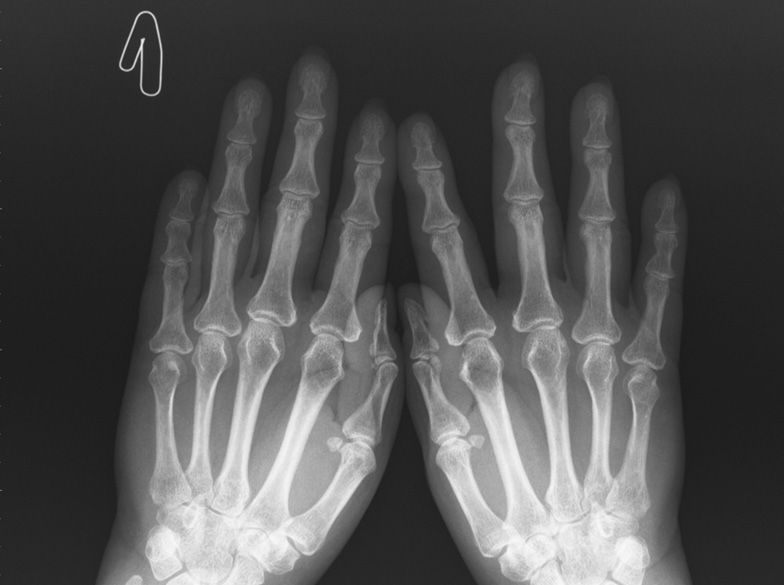

A clinical case of the onset of RA in a patient who underwent NCI was presented. Patient O., 60 years old, had NCI (confirmed by the PCR method) of moderate severity in October 2020, complicated by bilateral interstitial polysegmental pneumonia (respiratory failure of I–0 degrees). In November 2020, pains and swelling appeared in the left knee joint, followed by pains of an inflammatory nature in the right knee joint, wrist joints, and interphalangeal joints of the hands. Morning stiffness in the joints did not arrest for >30 min. She received Cartiflex at 1 sachet for 1 month and used ointments with NSAIDs without significant effect. According to laboratory data, an increased ESR up to 28 mm/h was noted. The patient was referred for hospitalization to clarify the diagnosis and treatment at the end of January 2021. Hospital: examination revealed symmetrical synovitis of the wrist joints, interphalangeal joints of the hands, left knee joint, and positive compression symptoms of the hands and feet. Pain syndrome on a visual analog scale was 8 points. The laboratory test revealed an increased level of CRP up to 12.3 mg/l, rheumatoid factor up to 89.9 IU/ml, and antibodies to ACCP over 200 IU/ml. Initial manifestations of arthritis are observed according to the X-ray data of the hands and feet (Fig. 4, 5).

Fig. 4. X-ray of the hands of patient O., age 60 / Рис. 4. Рентгенография кистей пациентки О., 60 лет

Periarticular soft tissues, mainly in the area of the interphalangeal joints of both hands, are indurated and expanded. Moderate periarticular osteoporosis was noted. Joint spaces are narrowed in all joint groups. The joint spaces of the distal interphalangeal joints of both hands are sharply narrowed, without subluxations. Single cyst-like lucencies are found in the interphalangeal joints, metacarpophalangeal joints, and small joints of the wrist, without convincing data for erosion (see Fig. 4).